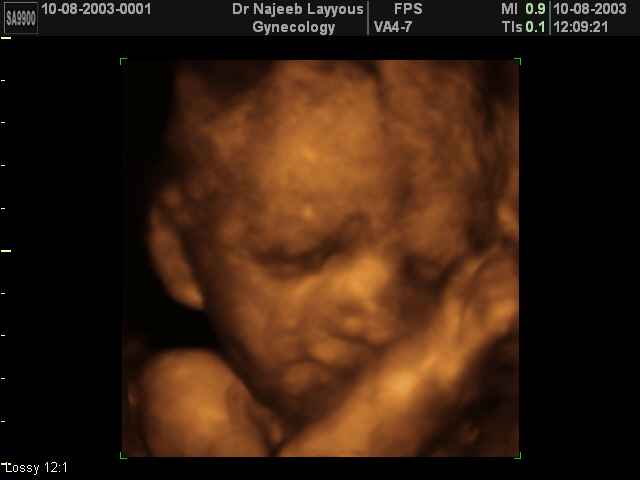

3D Fetal Face Ultrasound Scan Photos